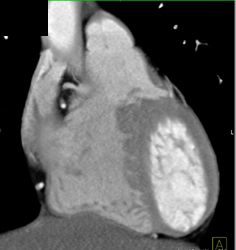

Diagnosis

Normal RCA